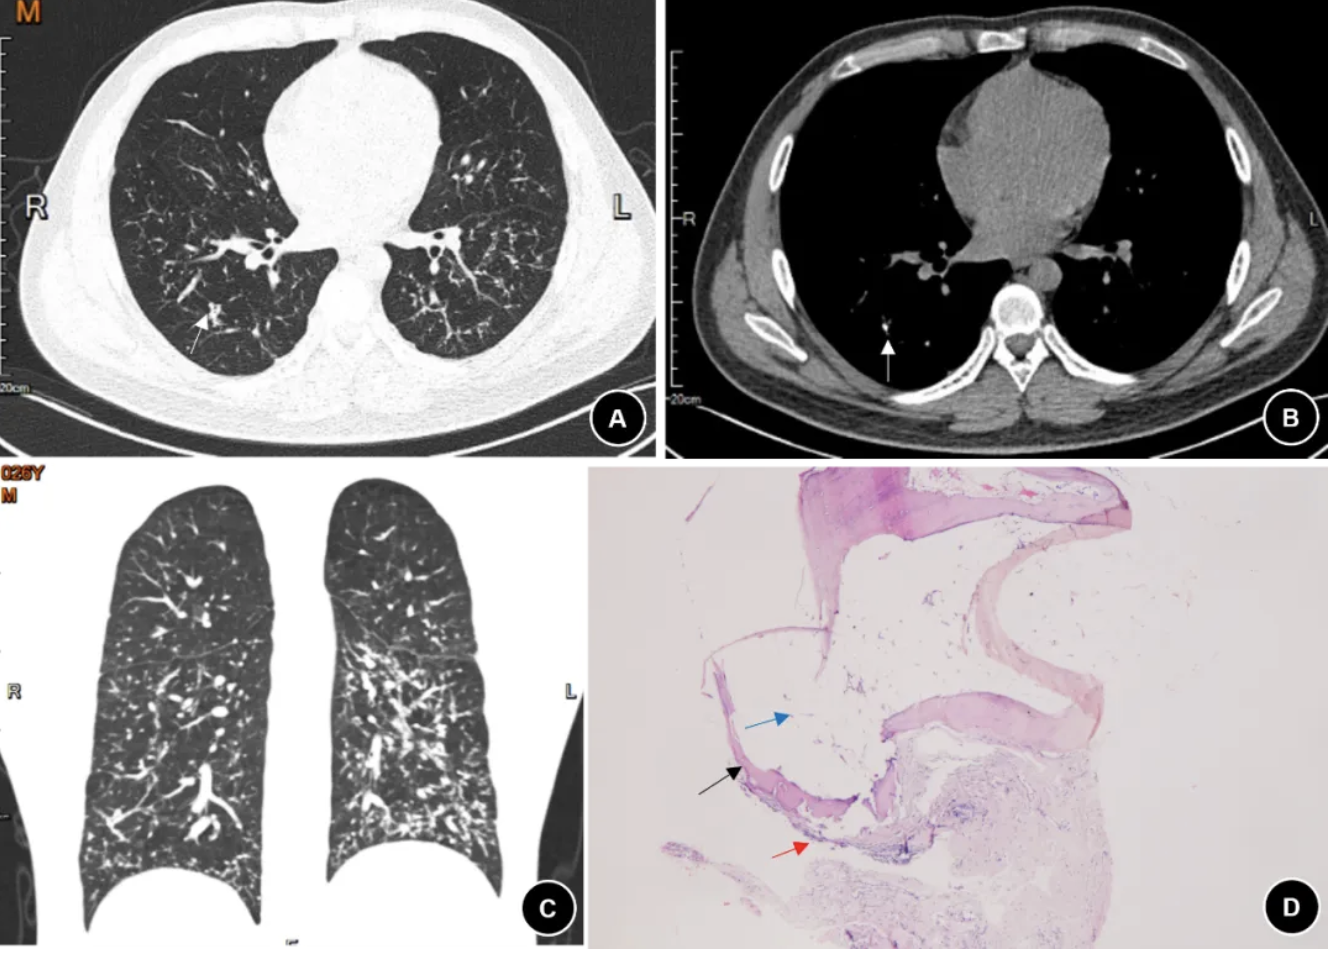

图 3. (例3患者)2023年11月胸部CT肺窗(A)、纵隔窗(B)、冠状面(C)显示双肺弥漫性高密度小结节伴钙化及细线状影,分布较稀疏(白色箭头); 2024年3月骨ECT显示,前位局部(D)、后位局部(E)示双肺放射性摄取弥漫性增高;(F)TBCB左下肺组织病理显示肺内见一处成熟骨组织(黑色箭头)(HE染色 ×100)。

4. 胸部影像学及肺功能表现:4例的胸部CT(图1-4 A-C)主要表现为双肺弥漫性高密度小结节伴钙化、散在分支样细线状影、胸膜轻度增厚。其中2例患者完善99mTc-亚甲基二膦酸盐(Methylene diphosphonate, MDP )全身骨显像(ECT)发现双肺放射性摄取弥漫增高,考虑骨外摄取(图2-3 D-E)。肺功能测试显示3例轻度阻塞性通气功能障碍, 1例限制性通气功能障碍,3例伴弥散功能轻度下降(表2)。

5. 病理学表现:4例诊断均经肺活检病理结果证实。1例在胸腔镜下行外科肺活检(Surgical lung biopsy, SLB),术中发现胸膜表面弥漫性分布粟粒样质硬结节,行楔形切口留取样本;2例行经支气管冷冻肺活检(transbronchial cryobiopsy, TBCB),获得3-4块直径约0.5 cm的肺组织标本;1例行经支气管肺活检(Transbronchial lung biopsy, TBLB)。病理主要表现为镜下观察到肺内成熟骨组织(黑色箭头),其中部分可见脂肪组织(蓝色箭头)(图1D、2F,、3F、4D)。